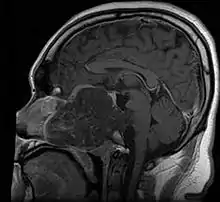

Anatomy

- In adults, remnants of notochord are present as the nucleus pulposus of the intravertebral discs, and distribution of tumors matches distribution of the remnants

- ~35% in sphenooccipital region (almost always involving clivus)

- 15-30% in vertebral column

- 30-50% in sacrococcygeal region

- Skull base:

- May be intracranial or extracranial, with mass effect symptoms depending on location

- Headaches and/or facial pain are common

- Pituitary insufficiency, hemianopsia/diplopia, cranial nerve deficits, nasal stuffiness.